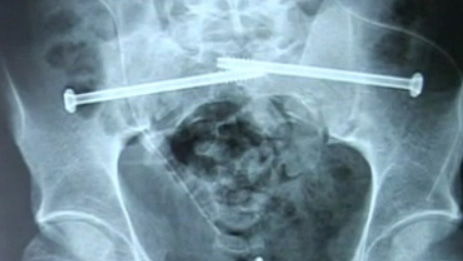

Mike Booth highsided his CBR600RR at Brands Hatch in the National Superstock 600 race and was hit by another rider. The crash broke Booth's pelvis and disconnected his spine from his pelvis, he has spent weeks in a wheelchair and undergone intensive surgery. His spine is now held in place with two bolts.